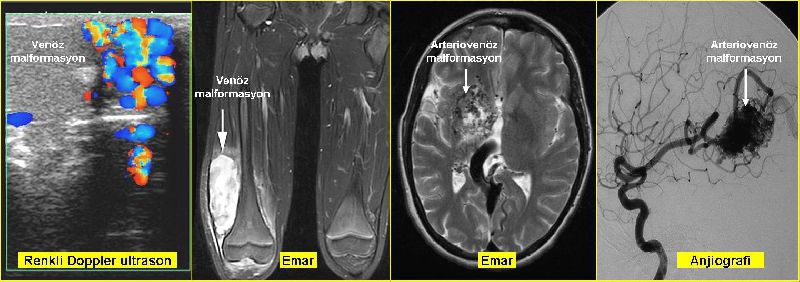

Tanı, görüntüleme: Cilde yakın olan malformasyonlarda en pratik yöntem renkli Doppler ultrasonografidir. Bu yöntemle malformasyonun yerleşimi, boyutları ve düşük akımlı mı yüksek akımlı mı olduğu ayırt edilebilir. Daha sonra genellikle MR yapılır. MR ile malformasyonların boyut, uzanım ve çevre dokularla ilişkisi daha iyi değerlendirilebilir. Ciltten derinde olan malformasyonlarda ise MR daha iyi bilgiler verir. Ancak düşük-yüksek akım ayrımı için genellikle renkli Doppler yapmak gerekir.

Damar malformasyonlarında radyolojik görüntüleme yöntemleri.

Beyindeki damar malformasyonları ve fistülleri en iyi MR ile görüntülenebilir. MR dan sonra, besleyici atardamarları ve kanı alan toplardamarları daha iyi tesbit etmek için genellikle klasik anjiografi yapılır.